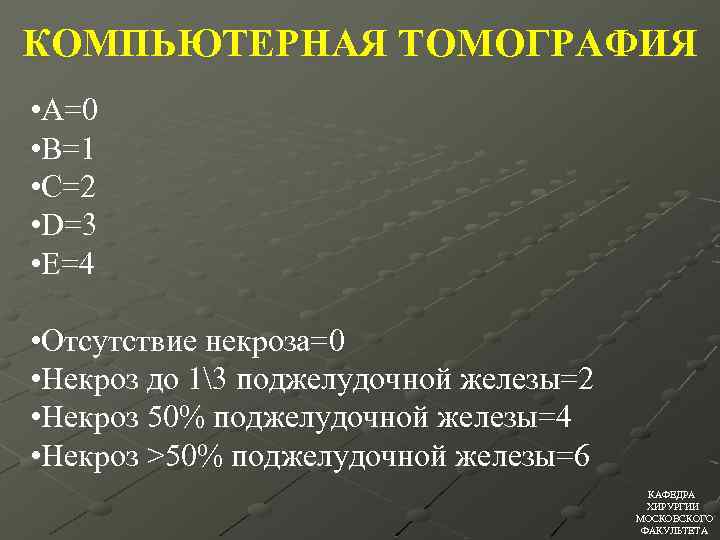

КОМПЬЮТЕРНАЯ ТОМОГРАФИЯ • А=0 • В=1 • С=2 • D=3 • Е=4 • Отсутствие некроза=0 • Некроз до 13 поджелудочной железы=2 • Некроз 50% поджелудочной железы=4 • Некроз >50% поджелудочной железы=6 КАФЕДРА ХИРУРГИИ МОСКОВСКОГО ФАКУЛЬТЕТА

КОМПЬЮТЕРНАЯ ТОМОГРАФИЯ • А=0 • В=1 • С=2 • D=3 • Е=4 • Отсутствие некроза=0 • Некроз до 13 поджелудочной железы=2 • Некроз 50% поджелудочной железы=4 • Некроз >50% поджелудочной железы=6 КАФЕДРА ХИРУРГИИ МОСКОВСКОГО ФАКУЛЬТЕТА

КОМПЬЮТЕРНАЯ ТОМОГРАФИЯ • 1 -2 балла – вероятность тяжелого панкреатита тяжелыми осложнениями невозможна • 3 -6 баллов – вероятность тяжелого панкреатита с тяжелыми осложнениями мала • 7 -10 баллов – вероятность тяжелого панкреатита с тяжелыми осложнениями 92%, летальность – 17% КАФЕДРА ХИРУРГИИ МОСКОВСКОГО ФАКУЛЬТЕТА

КОМПЬЮТЕРНАЯ ТОМОГРАФИЯ • 1 -2 балла – вероятность тяжелого панкреатита тяжелыми осложнениями невозможна • 3 -6 баллов – вероятность тяжелого панкреатита с тяжелыми осложнениями мала • 7 -10 баллов – вероятность тяжелого панкреатита с тяжелыми осложнениями 92%, летальность – 17% КАФЕДРА ХИРУРГИИ МОСКОВСКОГО ФАКУЛЬТЕТА